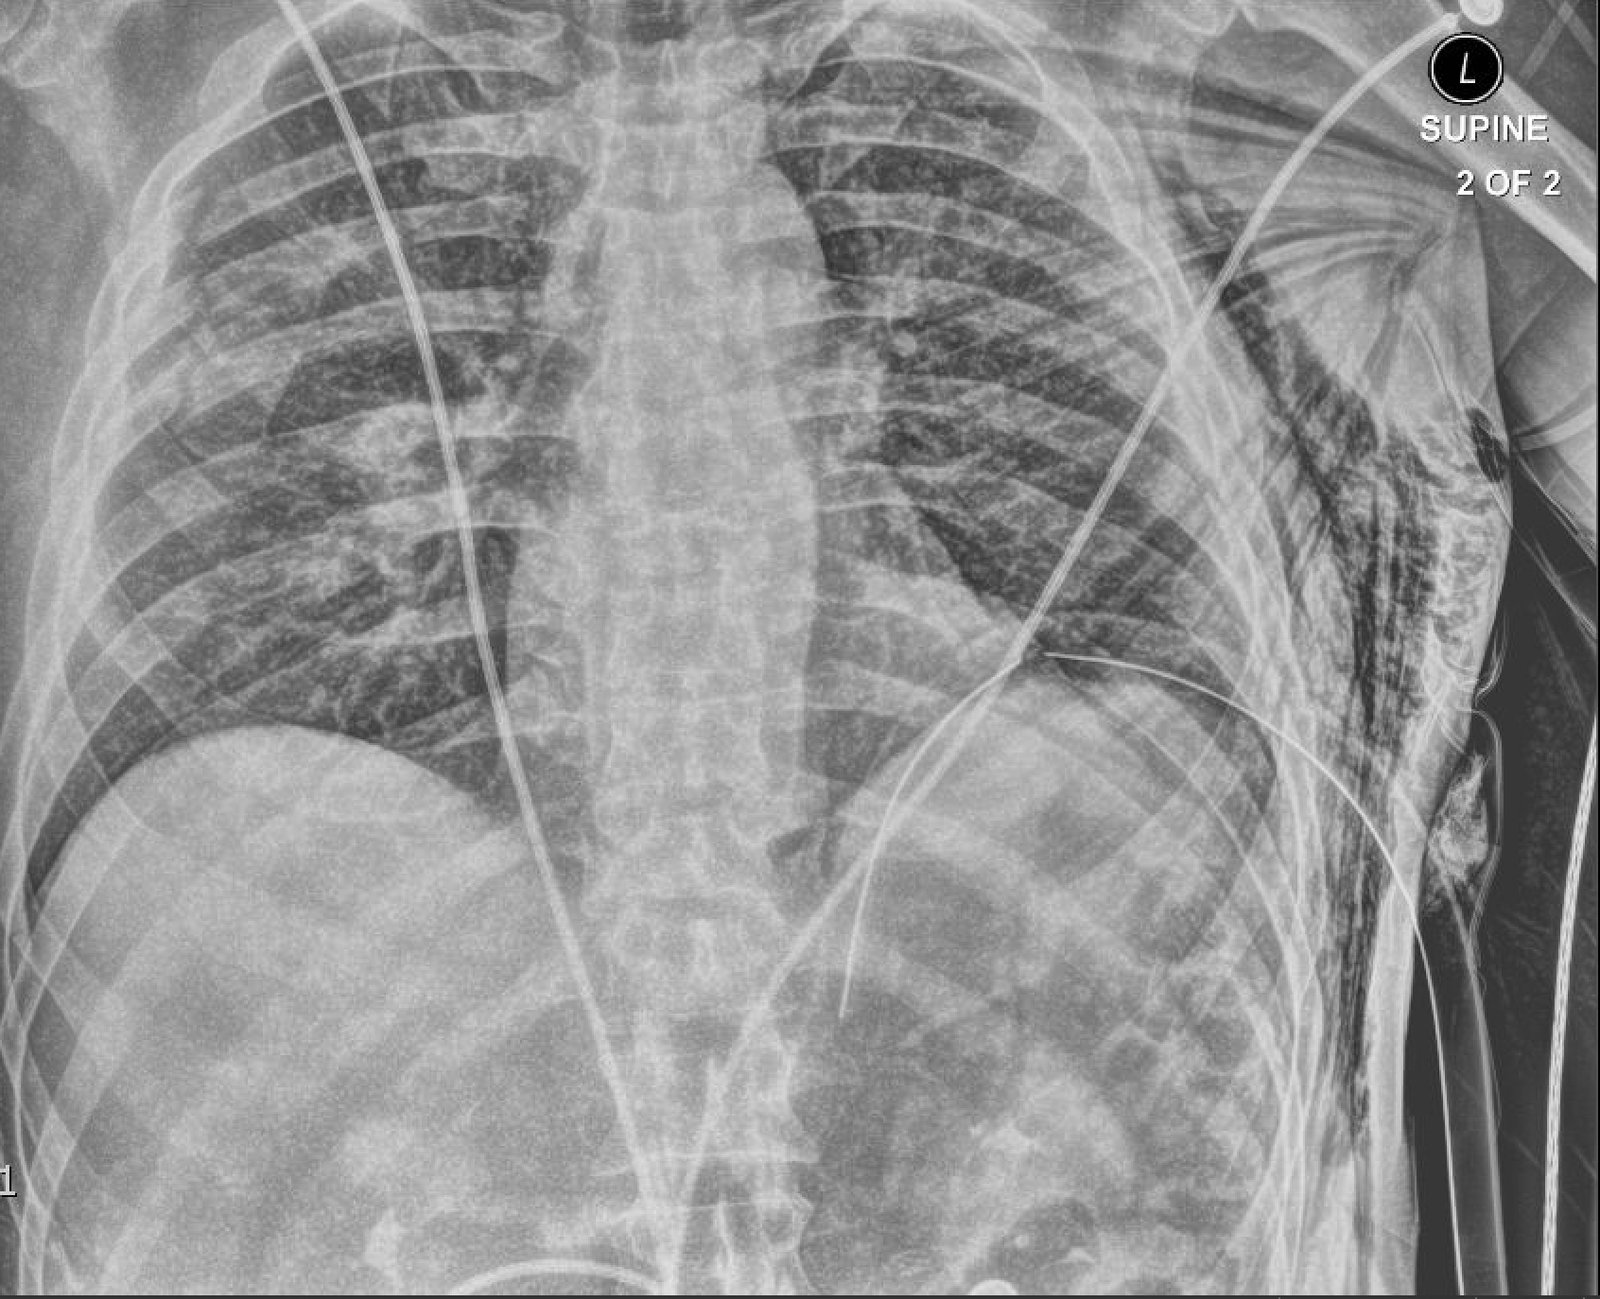

Plain film anteroposterior (AP) radiography of the chest shows left-sided subcutaneous emphysema (red arrow) with overlapping muscle striations of the pectoralis major (green arrow). After chest tube placement (blue arrow), AP chest radiography shows persistent left-sided subcutaneous emphysema (red arrow). CT of the chest shows pneumomediastinum (blue arrow), left apical pneumothorax (pink arrow), and subcutaneous emphysema (red arrow) at the level of T2. At the level of T6, rib fractures can be visualized on the CT (yellow arrow). At the level of T8, left sided pneumothorax is also seen (pink arrow) as the absence of lung tissue on CT.

In this patient, given the findings of multiple bilateral rib fractures, bilateral hemothorax/pneumothorax and multiple spine fractures, bilateral chest tubes were placed which had immediate output. The patient was admitted to surgical intensive care unit for chest tube management, pulmonary hygiene and further management of his other injuries.